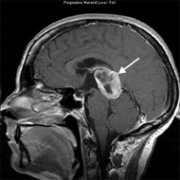

垂体瘤 作为颅内较常见的肿瘤之一,其发生率仅次于脑胶质瘤和脑膜瘤,约占颅内肿瘤的8%-15% 。尽管垂体瘤大多数为良性肿瘤,但部分患者术后已消失的...